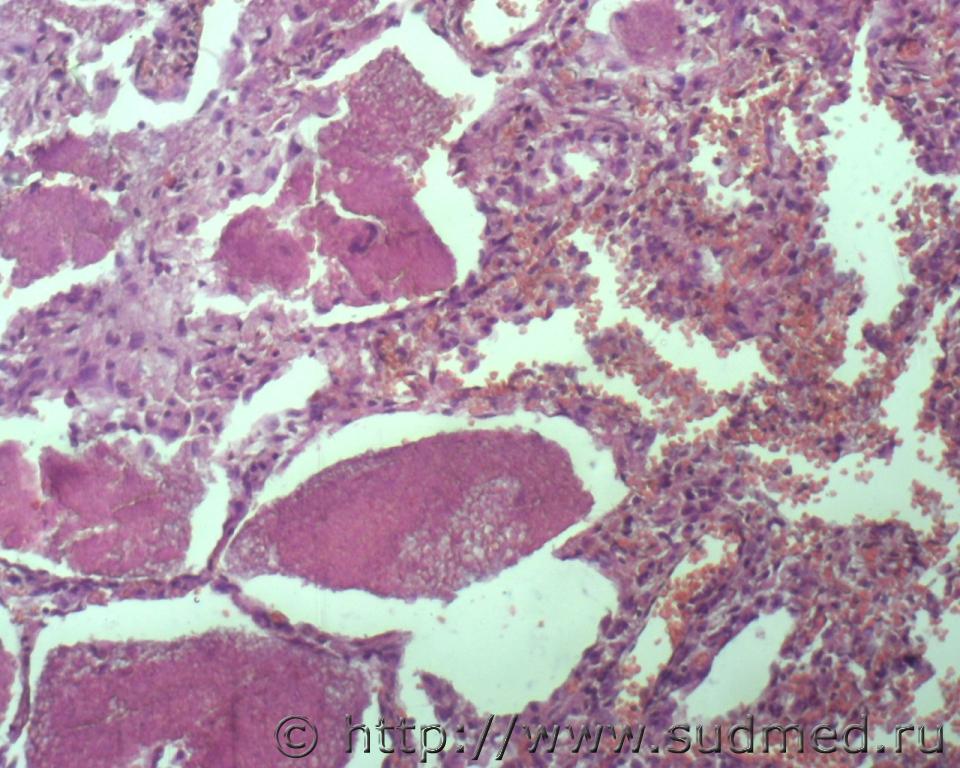

Реканализация тромба артерии лёгкого.